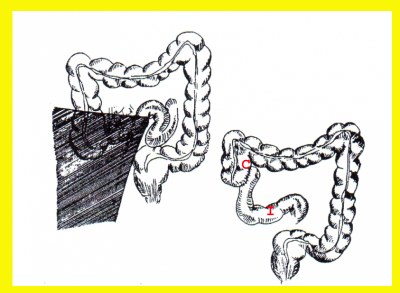

- Ileotransversostomy - שבו יוצרים קשר חדש בין לולאת מעי דק תיכונה (פרוקסימלית) לנגע לבין הכרכשת הרוחבית. ניתוחים אלה מבצעים בעיקר כאשר לחולה יש חסימה שלמה של המעי הדק ומצבו הכללי או הממצאים בבטן אינם מאפשרים ניתוח נרחב יותר. הפסקת מעבר המזון דרך הקטע הנגוע מאפשרת ריפוי המעי והקלה בתסמינים (איור 4.1).

- Bypass by Exclusion - בניתוח זה מנתקים את קטע המעי הנגוע מהקטע הבריא. את הקטע הבריא מחברים לכרכשת הרוחבית. הקטע הנגוע נסגר בקצהו התיכון (הפרוקסימלי), והוא מתנקז למעי העיוור (צקום) (איור 4.2). הפרדה מושלמת זו בין שני חלקי המעי מונעת מעבר של מזון דרך הקטע הנגוע, ובמשך השנים הוא מידלדל. יש דיווחים בספרות על שכיחות גבוהה יותר של שאתות ממאירות בקטע זה של המעי. ניתוחי מעקף מבוצעים רק בחולים מבוגרים בעלי סיכון גבוה לניתוח או בחולים שבוצעו בהם ניתוחים חוזרים ומעוניינים לשמר בהם חלקים גדולים ככל האפשר מהמעי הדק. ניתוחים אלה מבוצעים גם בחולים בעלי מורסות המצריכות בידוד של קטע המעי הנגוע בלי לכורתו.

ניתוחים שמרניים אחרים הם: כריתות מוגבלות של הקטעים הנגועים במעי הדק בחולים שיש בהם נגעים מרובים במעי הדק (Skip lesions), שהמרחק ביניהם הוא פחות מ-10 ס"מ. מומלץ לכרות את כל הקטע הנגוע, ואולם אם המרחק גדול יותר, מומלץ להשאיר את הקטע "הבריא" שבין הנגעים ולחבר את הקטעים שנותרו (איור 3.4). בחולים עם היצרויות בקטעים קצרים אפשר לבצע Strictureplasty.